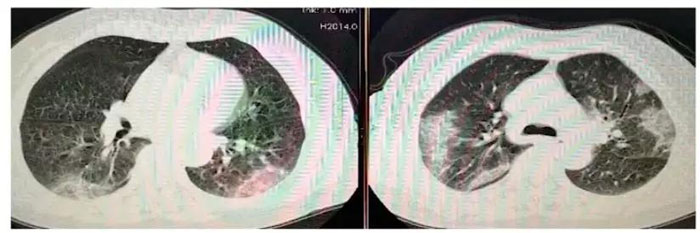

5分:双肺胸膜下区多发斑片状磨玻璃密度影,边界清楚,可短期(几天内)演变为大片实变或者逐渐吸收、纤维化,强烈提示新型冠状病毒感染性肺炎。

临床意义:无论核酸检测是否阳性,依照2019新型冠状病毒(2019-nCoV)感染肺炎治疗,传染病病房隔离。亲密接触者隔离观察。